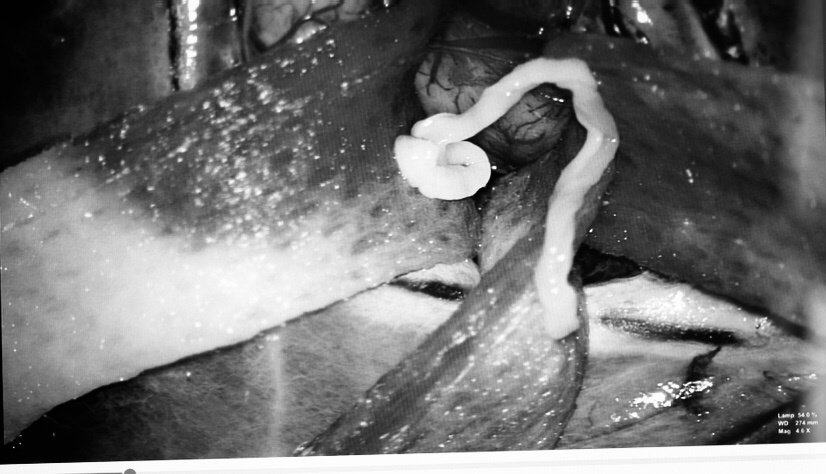

Khi mở ra tinh hoàn đã hoại tử tím đen do xoắn không có khả năng bảo tồn. Các bác sĩ Trung tâm Nam học đã tiến hành cắt tinh hoàn xoắn hoại tử và cố định tinh hoàn còn lại. Hiện tại, tình trạng bệnh nhân ổn định và vừa xuất viện.

| Các bác sĩ Trung tâm Nam học tiến hành mổ cấp cứu cho bệnh nhân. Ảnh: BVCC. |